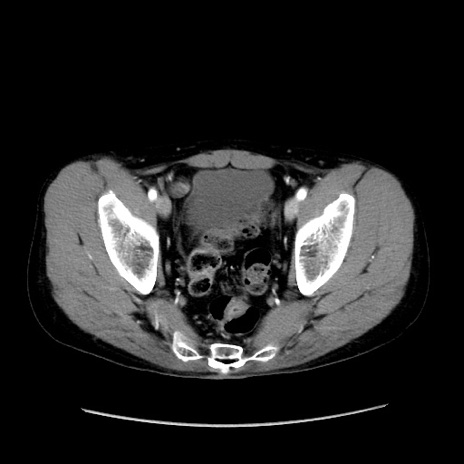

症例37(横断像)

【症例】40歳代 男性

【主訴】腹痛

【現病歴】4時間ほど前に電車に乗車中に臍部上より腹痛出現。徐々に増悪し起立困難となり、救急外来受診。生ものは数日食べていない。今朝お雑煮を食べた。

【身体所見】BT 36.8℃、BP 117/84mmHg、HR 91/min、SpO2 97%、苦悶様、腹部:臍上部広範囲圧痛あり、反跳痛±

【データ】WBC 8100、CRP 0.03